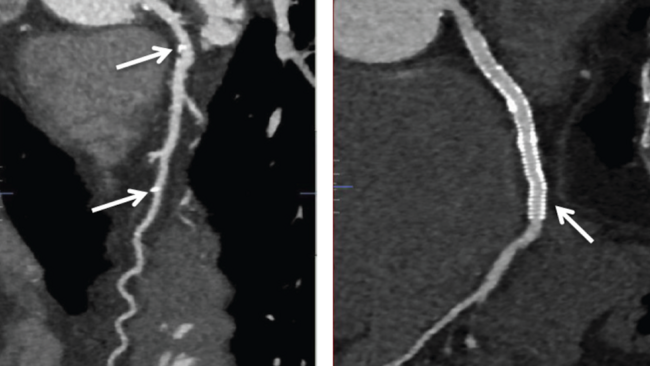

A 72-year-old gentleman presented with angina. He had previously undergone percutaneous coronary intervention (PCI) to the right coronary artery and left circumflex artery (LCX) with drug-eluting stents. Coronary angiography revealed a long segment of moderate stenosis in the proximal to mid left anterior descending artery (LAD) (Figure 1A). This was treated with Absorb bioresorbable vascular scaffolds (BVS; Abbott Vascular) (Figure 1B) with the use of intravascular ultrasound to confirm adequate stent expansion. He represented 5 years after his PCI with atypical symptoms. A computed tomography coronary angiogram showed the BVS were no longer visible and only the platinum markers were seen (Figure 1C). The scaffolds had been completely reabsorbed, allowing the use of non-invasive imaging to obtain high-quality diagnostic images not affected by artefact, as seen with the DES in the LCX (Figure 1D) preventing the vessel being assessed with the same clarity.